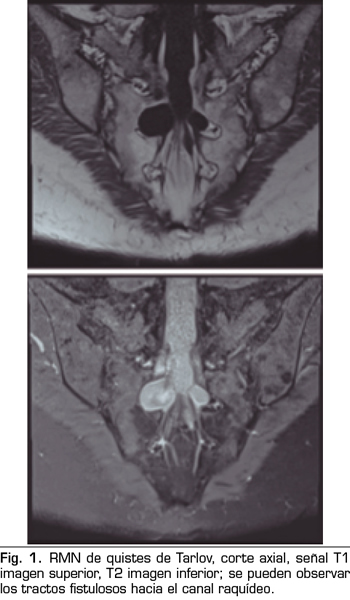

Se realiza una RMN donde no se observan alteraciones estructurales que justifiquen las dolencias que presenta. Como hallazgo casual se describen quistes de Tarlov a nivel de S2. Se solicita una valoración por el servicio de neurocirugía, quienes dudan que la clínica sea consecuencia de los quistes (Figuras 1 y 2).

No obstante, debemos tener en cuenta las variaciones anatómicas como son los quistes de Tarlov, a expensas de las capas más internas de las meninges, la piamadre y el aracnoides. Estos quistes principalmente se sitúan en la zona sacra y lumbar, y suelen diagnosticarse de manera incidental en el transcurso de una RMN. Aunque la clínica producida por los mismos no es frecuente, se deben tener en cuenta como posible diagnóstico diferencial ante posible dolor lumbar crónico.